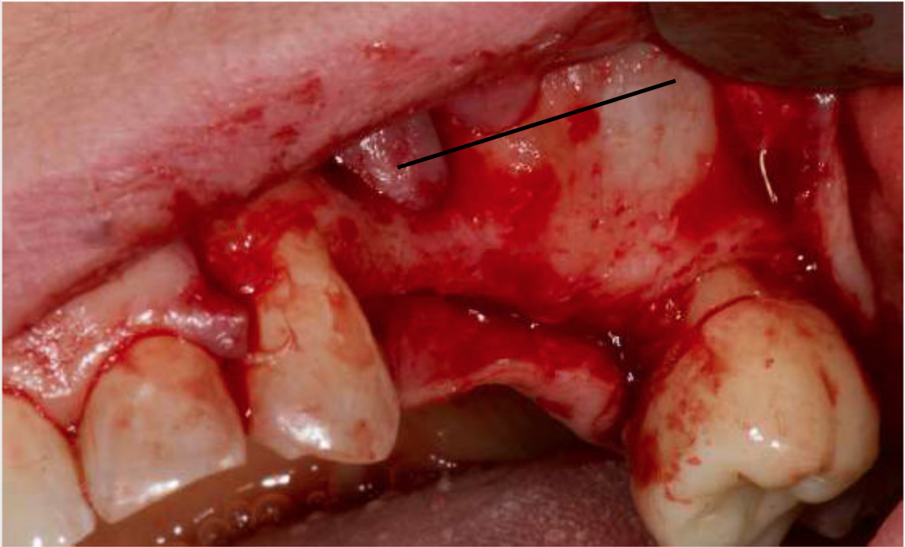

In fase preoperatoria è stato prescritto aerosol (2 volte al giorno per 7 giorni) con beclometasone dipropionato (Clenil 0,8 mg/2 ml) e soluzione ipertonica (Libenar 22g/l) a partire da 7 giorni prima dell’intervento e antibiotico (Amoxicillina 1 g - ogni 12 ore a partire dal giorno precedente l’intervento per 6 giorni). È stato eseguito il rialzo di seno mascellare del secondo quadrante per via laterale abbinato a una contestuale tecnica di GBR/Guided Bone Regeneration (Figg. 4-6). Come sostituto osseo è stato utilizzato lo xenoinnesto bovino Re-Bone® (Ubgen, Padova, Italy) da 1 g con granuli cortico-spongiosi 0,25-1 mm (Figg. 7, 8, 11). Questa metodica è stata abbinata a Shelter ® membrana in pericardio bovino (Ubgen, Padova, Italy) fissata poi con appositi pins ritentivi (Figg. 12, 14, 15). Terminata la tecnica di GBR, sono stati suturati i lembi (Vicryl, 4/0, Johnson & Johnson Int.) (Fig. 16).

L'evoluzione della tecnica chirurgica nell’approccio attraverso finestra laterale all’osso mascellare per il sollevamento della membrana del seno, ha lo scopo di ridurre le complicanze che possono compromettere l’esito dell’intervento e la sopravvivenza dell’impianto. La chirurgia piezoelettrica ha dimostrato il vantaggio di ridurre drasticamente il tasso di perforazione, aumentando così la percentuale di successo complessivo della tecnica di rialzo di seno mascellare15 (Figg. 19-22).